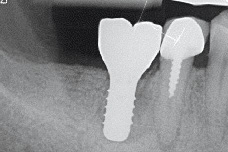

IMPLANTOLOGIE, PARODONTOLOGIE A ÚSTNÍ A CMF CHIRURGIE

- Sinus lift

- augmentace alveolu

- Intraoseální vady

- Augmentace extrakční rány

- Kostní defekty

- Furkační defekty